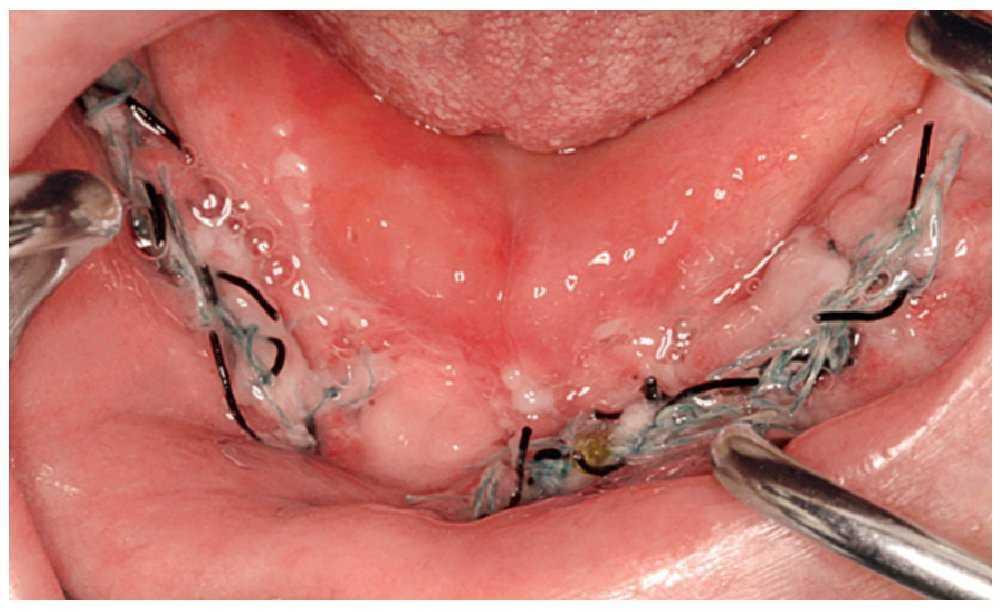

En lesiones pequeñas y dependiendo del tamaño del defecto se puede realizar una revisión local con limpieza y eliminación de los secuestros óseos y el alisado de los bordes de la herida. En este contexto se debe tener en cuenta que el tamaño del secuestro siempre es mayor que la zona ósea expuesta (figs. 6a y 6b). En los casos no complicados, se procede a continuación a la cobertura plástica con mucosa bien vascularizada.

Figura 6. Secuestro alrededor de un implante, situación clínica (a) y aspecto macroscópico después de la eliminación del secuestro (b).

En defectos de mayor tamaño o en caso de fracasar el tratamiento local se practicará una resección ósea en medio hospitalario y se administrarán antibióticos por vía parenteral (figs. 7a a 7c).

Figura 7a. Necrosis extensa del maxilar asociada a bifosfonatos, imagen preoperatoria.

Figura 7b. Aspecto después de la eliminación del secuestro y cobertura plástica con mucosa bien vascularizada.

Figura 7c. Estado cuatro semanas después de la intervención, hueso con recubrimiento mucoso intacto.